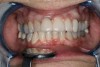

Fig 1. Miller Class I recession on tooth No. 11 (Fig 1) treated with tuberosity CTG (Fig 2). Note this CTG (which is the tuberosity CTG from Fig 5) was placed before the practitioner developed thinning techniques, so a keloid-like appearance was observed even 1 year after grafting.

Figure 1

Fig 2. Miller Class I recession on tooth No. 11 (Fig 1) treated with tuberosity CTG (Fig 2). Note this CTG (which is the tuberosity CTG from Fig 5) was placed before the practitioner developed thinning techniques, so a keloid-like appearance was observed even 1 year after grafting.

Figure 2

A complication in using CT from the tuberosity reported in the literature is a tendency for clinicians to harvest tissue that is too thick.12 This can result in a keloid-like appearance similar to what may occur with an EPG. This excess thickness can be unesthetic (Figure 1 and Figure 2) and subsequently require a gingivoplasty to remove the superfluous tissue.12 This problem may perhaps be alleviated with proper thinning of the graft prior to insertion into the recipient area.